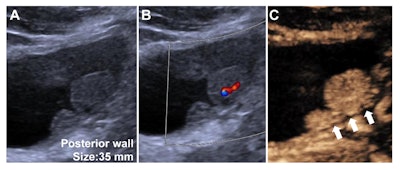

Contrast-enhanced ultrasound (CEUS) Vesical Imaging-Reporting and Data System (VI-RADS) category 3 findings in a 40-year-old male with non-muscle-invasive high-grade urothelial carcinoma. (A) Grayscale US image obtained using a convex array probe (5C1) through a transabdominal approach showed a 35-mm lesion at the bladder posterior wall. (B) Color Doppler US image showed inner vascularity within the lesion. (C) Contrast-enhanced US image showed well-defined continuous layer of hypo-enhanced muscularis propria (white arrows) without vascular stalk on contrast-enhanced US or early hyper-enhanced continuous inner layer. The observation was assigned to VI-RADS 3 based on contrast-enhanced US by the readers devising the CEUS VI-RADS. Image and caption courtesy of the RSNA.